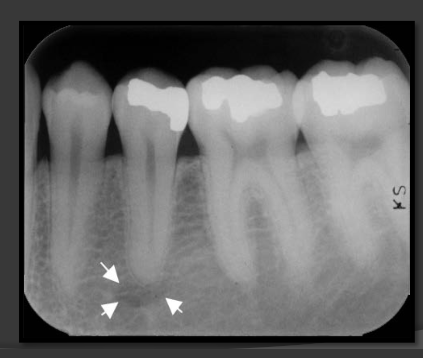

How does the mental foramen present in a radiograph?

Presents as small ovoid radiolucent areas near the apical region of the premolars in the mandible.